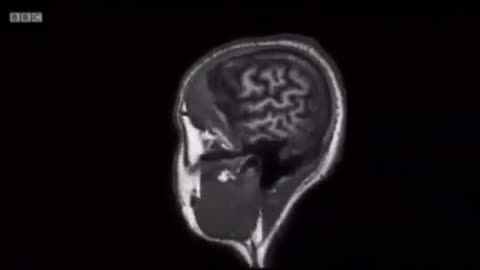

8. The Food Trap: How Ultra-Processed Diets Hijacked Our Biology

The Food Trap: How Ultra-Processed Diets Hijacked Our Biology